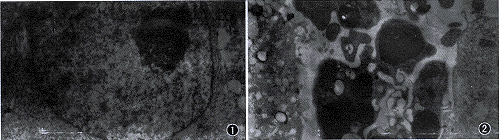

3.凋亡小体:电镜下观察, 对照细胞核呈圆形、规则,染色质分布均匀,可见1~2个核仁。紫杉醇作用24小时,部分细胞核染色质浓集,紧靠核膜,核膜内陷,不规则。细胞外可见凋亡小体,内有浓集染色质,胞浆物质浓缩(图1,2)。

图1 对照细胞核成圆形、规则,染色质分布均匀,可见1~2个核仁。 ×12 000

图2 紫杉醇(30 nmol/L)作用24小时后,细胞染色质浓集,不规则,可见凋亡小体。×7 100